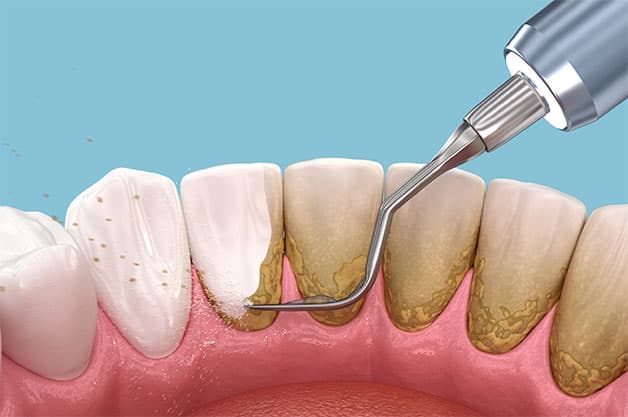

Sau đó, nhằm hạn chế số lượng vi khuẩn trong khoang miệng, tránh những biến chứng mà việc lấy cao răng có thể để lại, trước khi lấy cao răng, nha sĩ sẽ tiến hành làm sạch răng miệng cho bệnh nhân. Sau đó là quá trình lấy cao răng với thiết bị nha khoa chuyên dụng nhằm loại bỏ toàn bộ cao răng, mảng bám kể cả ở các vị trí khó nhìn. Quá trình này hiện nay hầu như được thực hiện bằng công nghệ hiện đại, không gây tổn thương cho răng lợi nên trước đó rất ít trường hợp cần dùng đến gây tê khi làm cao răng.

Sau quá trình lấy cao răng là việc làm nhẵn, làm bóng răng, nhằm giúp hạn chế quá trình mảng bám, cao răng hình thành. Đây là bước quan trọng và cũng là điểm khắc phục tình trạng răng bị lỗ hoặc không nhẵn bóng của các phương pháp lấy cao răng cũ trước đây.

Vệ sinh răng miệng là bước cuối để hoàn thiện việc lấy cao răng. Sau đó, các bác sĩ sẽ kiểm tra lại và hướng dẫn bệnh nhân thực hiện những vấn đề về việc chăm sóc răng đúng cách, phòng ngừa tình trạng cao răng và bệnh lý răng miệng.